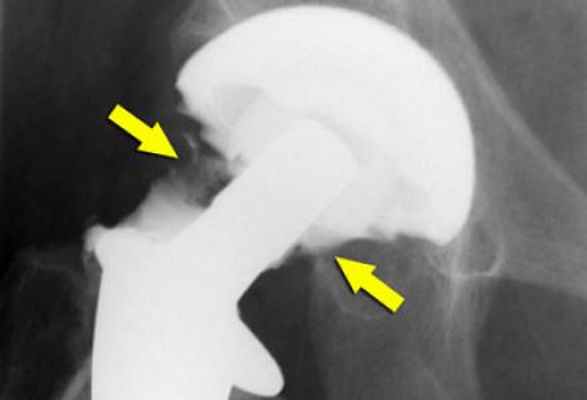

Смещение протеза

В результате данного явления вживленный имплантат не только теряет фиксацию и расшатывается, но и приводит к постепенному или резкому изменению длины ног. В таком случае требуется немедленная консультация у врача и повторная операция на конечности. К основным причинам можно отнести следующие:

- неправильная установка имплантата;

- недостаточный контакт между поверхностями сустава и протеза;

- сильные нагрузки на имплантат;

- непрочное соединение компонентов изделия.

Остеолиз

К образованию данного процесса может привести частичное или полное разрушение кости, которое наступает в результате взаимодействия компонентов протеза с живой тканью.